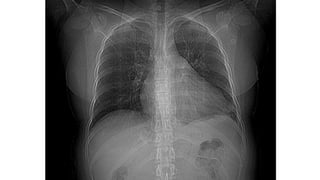

Rx de Tx

Ventajas Desventajas

Evita desplazamiento de pacientes

internados

Poca sensibilidad (en relación a

TC)

De gran utilidad en UTI Poco específica

Menor radiación Poco específica

De elección para seguimiento Score de gravedad poco prácticos

Rx de Tx VentajasDesventajas Evita desplazamiento de pacientes internados Poca sensibilidad (en relación a TC) De gran utilidad en UTI Poco específica Menor radiación Poco específica De elección para seguimiento Score de gravedad poco prácticos